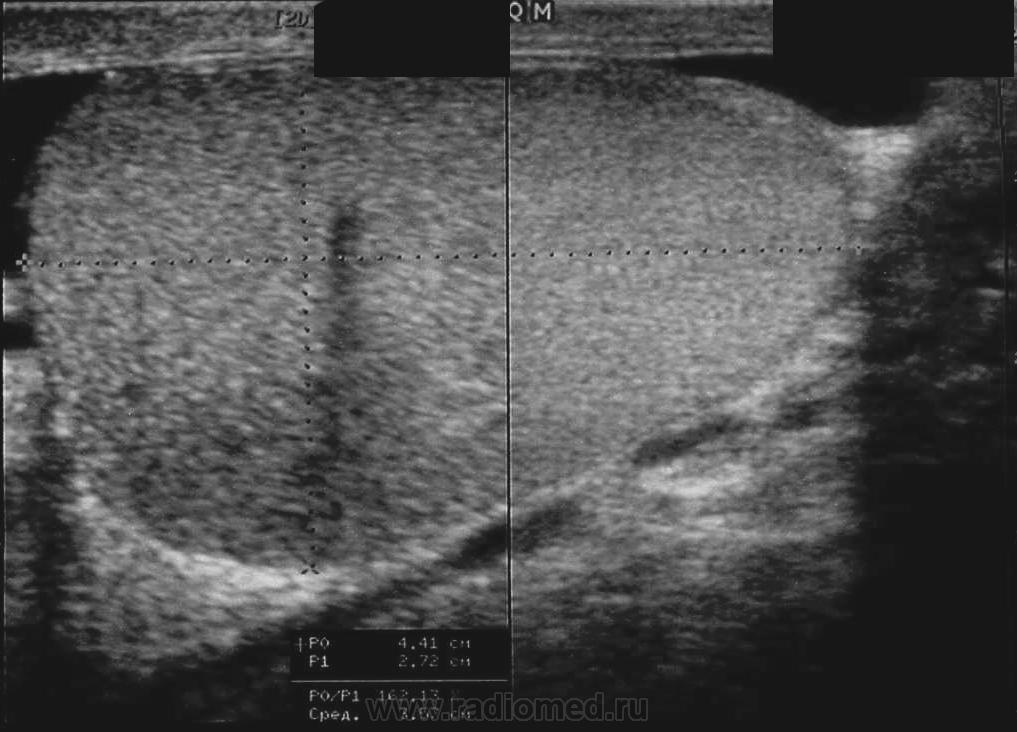

семинома?

Считаю, что семинома - не самый вероятный вариант, т.к. структура опухоли достаточно неоднородная, есть распространение на придаток и границы четкие.

Могу предположить, неоплазию правого яичка.

Я в заключении вынес на первый ряд карциному яичка.